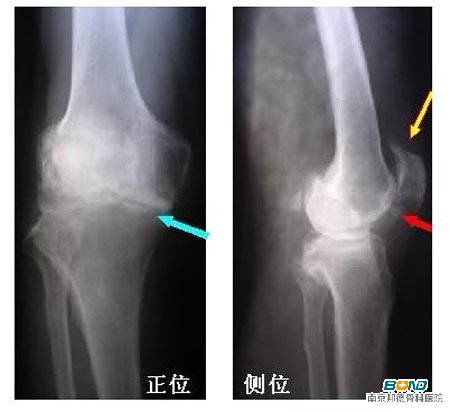

1、膝关节炎

膝关节炎是膝关节的常见疾病,骨关节炎的主要特征包括有软骨退行性病变和关节边缘骨赘的形成。一般表现有关节疼痛、压痛、强响、关节积液、活动受限、关节畸形以及可有不同程度的局部炎症。一般无全身的症状。 【膝关节炎的治疗方法有哪些?】

2、骨质增生

膝关节骨质增生是由外伤或自身免疫反应等因素引起,包括软骨的退行性变、软骨软化、糜烂,骨端暴露,滑膜、关节囊和肌肉的变化。起初疼痛多在长时间行走或上下楼梯时。之后,走平路也疼痛,活动不便,关节不稳;同时关节有响声。重者还有关节交锁现象。 【骨质增生可不可以不治疗?】